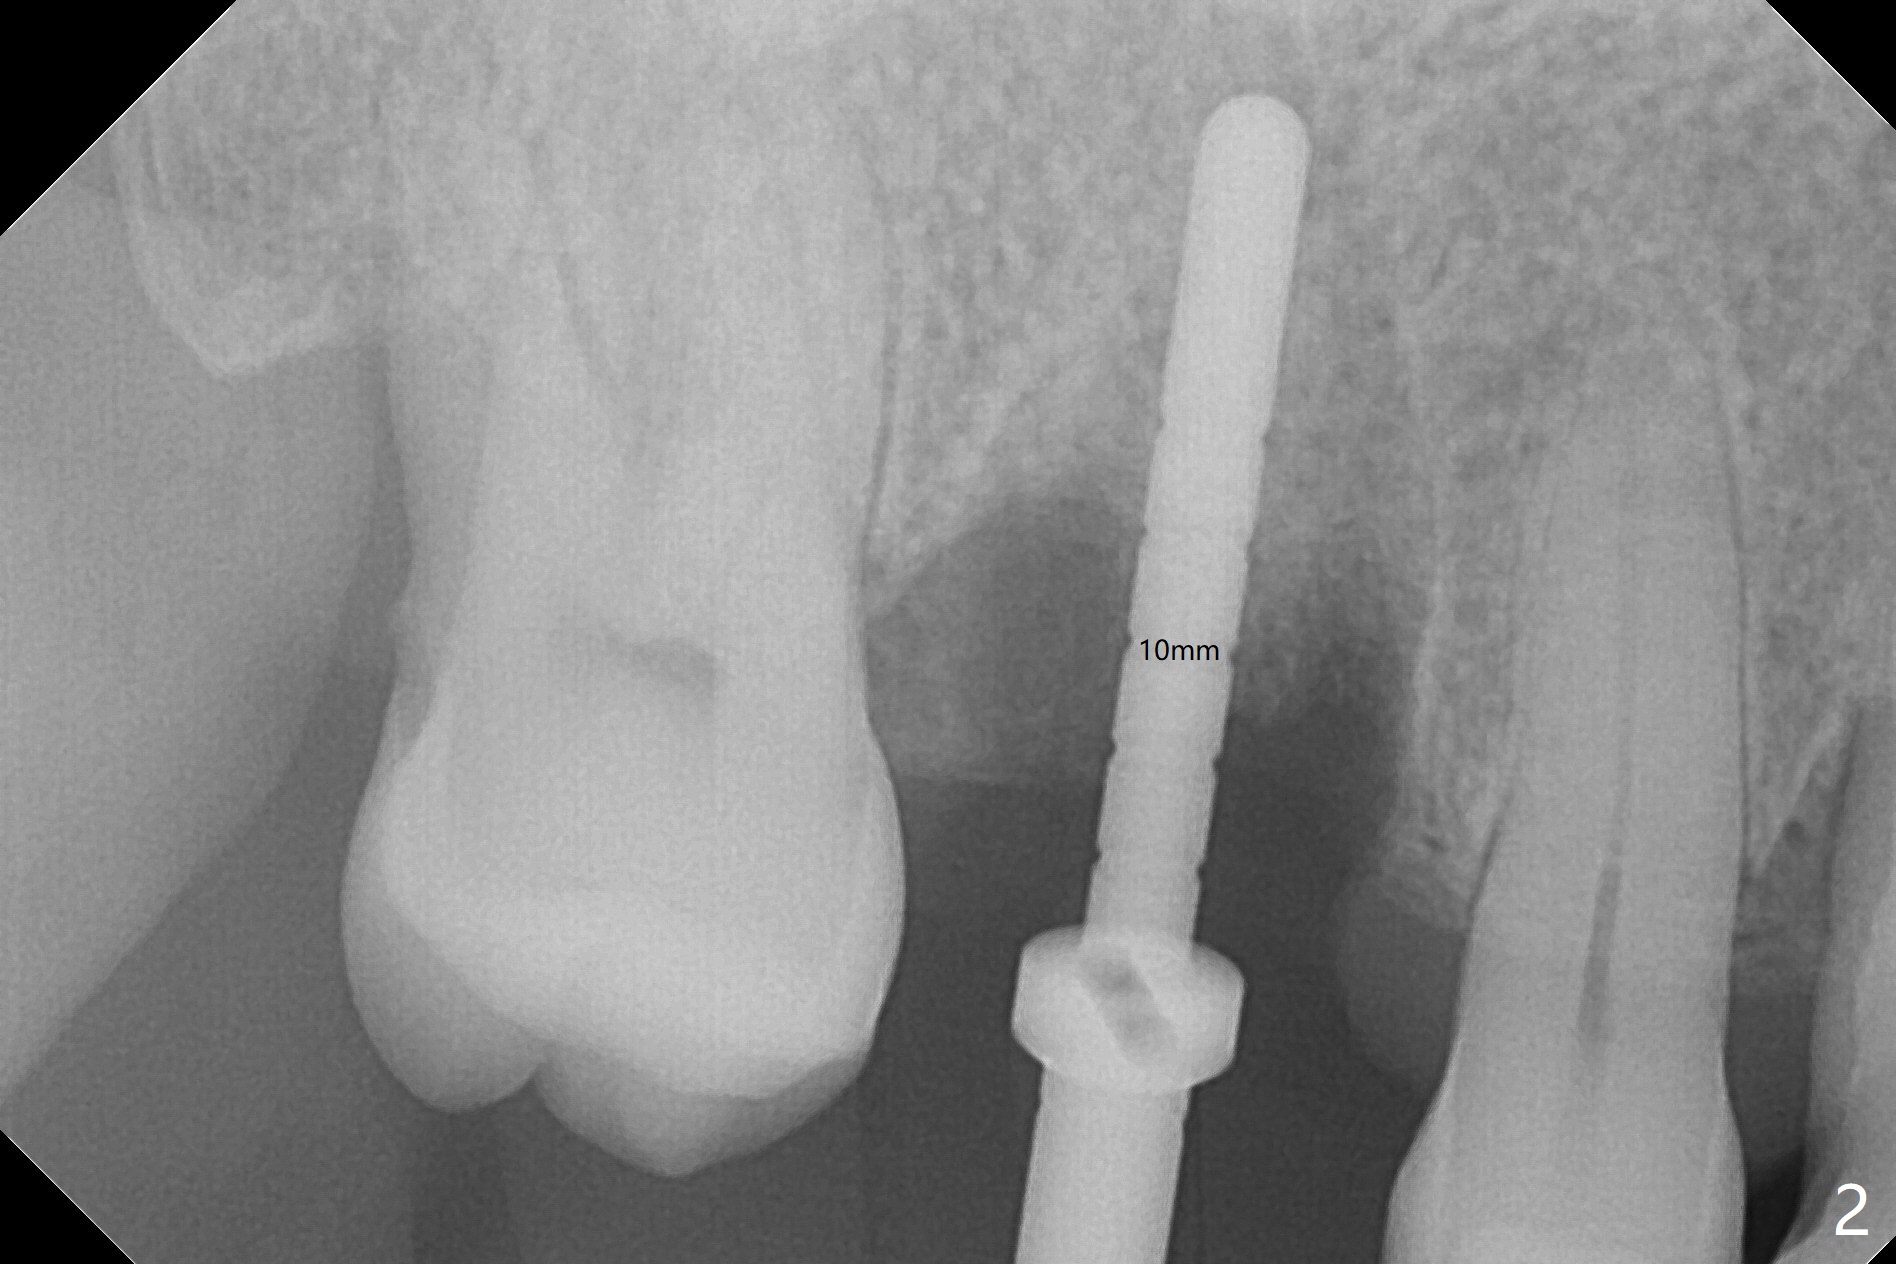

While the tooth #3 has a mesiodistal crack line, etiology may be due to chronic periodontitis with bruxism. After extraction, there is granulation tissue attached to the distobuccal (DB) root. The DB socket is larger than the mesiobuccal one (Fig.1). Osteotomy is initiated in the DB slope of the septum for 10 mm (Fig.2,3). Since there is ample apical bone, the depth of the osteotomy increases to 11.5 mm. When a 5x10 mm dummy implant is placed, primary stability is satisfactory (Fig.4 (yellow line: apical space)). The definitive implant remains the same dimension with deeper placement (Fig.5,6 (~ 20 Ncm)); with placement of a 6.5x4(3) mm abutment and Vanilla/Osteogen Graft (*), an immediate provisional is fabricated in place (without taking out for trimming) with sufficient clearance with the opposing dentition. It appears that the moderately long implant (10 mm) is able to achieve primary stability for immediate placement. When the provisional is removed 2 months postop, bone graft seems to be adhered to the socket (Fig.7). To improve local hygiene, the provisional does not return. The implant seems to have osteointegrated 3.5 months postop (Fig.8). The crown/abutment is loose approximately 1 year post cementation. Due to her daughter's contracting COVID 19, she postpones returning for approximately 1 year. The access hole is opened, crown/abutment (6.5x4(4) mm) removed, proximal contacts reduced, crown/abutment reseated without certainty. BW shows incomplete seating probably due to bony interference (Fig.9). A 5.5x4(4) mm can not be seated (bouncing, probably due to soft tissue interference). When a 4.5x5(4) mm abutment (UF) is seated, hand tightening is smooth, confirmed by BW (Fig.10). Two weeks later, the new crown is cemented intraorally. The crown/abutment is removed for cleaning. The abutment screw is torqued at 20 NCM.